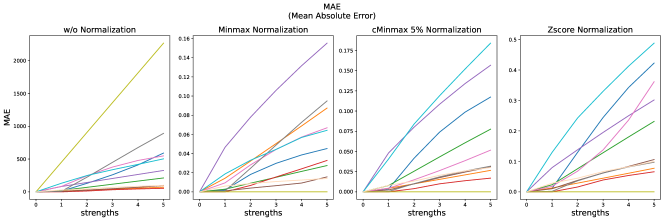

The results for all strengths are given in Figs. A.1-A.4. In Tab. 5 - 8, the results for distortions of maximal strength (s=5) are summarized.

For all applied distortions, all reference metric scores monotonously measure lower similarity for increasing distortion strengths.

Without applying any normalization, all metrics beside NMI are very sensitive to intensity shifts (see Tab. 5). However, with any normalization method, intensity shifts are fully compensated, and all metrics measure perfect similarity.

Across all normalization methods, all metrics are very sensitive to translation and not very sensitive to replace artifacts.

SSIM similarity scores for strong blurring are very high, compared to most other distortions.

Gaussian noise is better detected with Minmax normalization, while stripe artifacts seem to be less detected with Zscore normalization.

PSNR scores generally display only very small changes for strengths larger than 2 (see Fig. A.1). PSNR values are higher for Zscore normalization.

Images distorted with Gaussian blurring and ghosting artifacts receive very high PSNR similarity scores, especially with small distortion strengths.

All error metrics (MSE, MAE and NMSE) strongly vary in their value range, depending on the normalization method. They are consistently most sensitive to translation and then to bias field, and gamma transforms. As cMinMax partially compensates the effect of the gamma transforms, the error metrics hardly find dissimilarities in the gamma transformed images with this normalization.